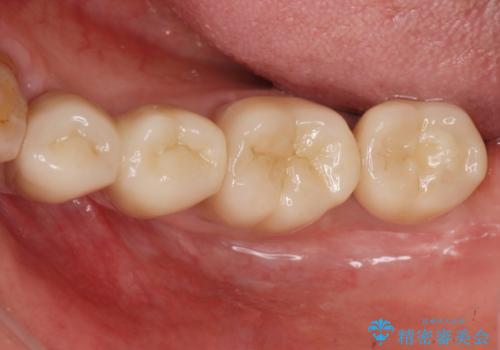

歯周病の問題が解決したのち、歯の揺れを抑えるべくセラミッククラウンで連結補綴をおこなっています。

再生療法を行ったことで、抜歯をされてもおかしくなかった歯を、残すことができました。